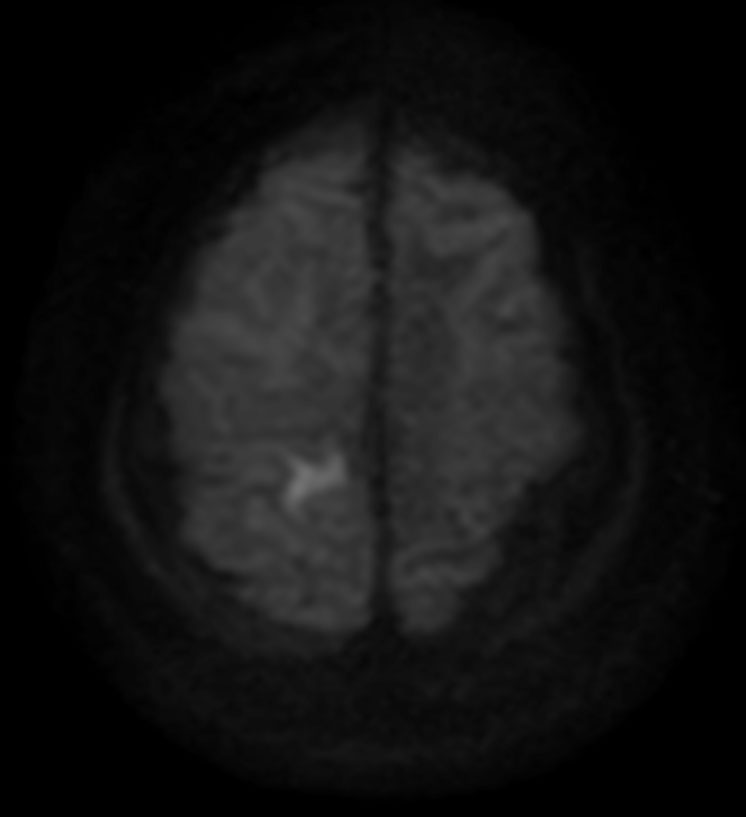

DWI TSE